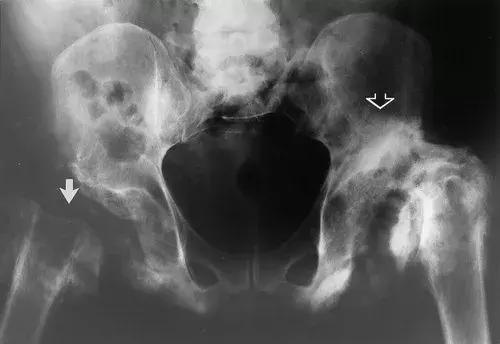

图23:28岁男性,T7以下截瘫,双侧神经性髋关节。正位X线片显示右侧髋关节萎缩,截肢外观(实心箭头),左侧臀部显示肥厚性硬化和碎裂(空心箭头)。 显示双侧脱位。